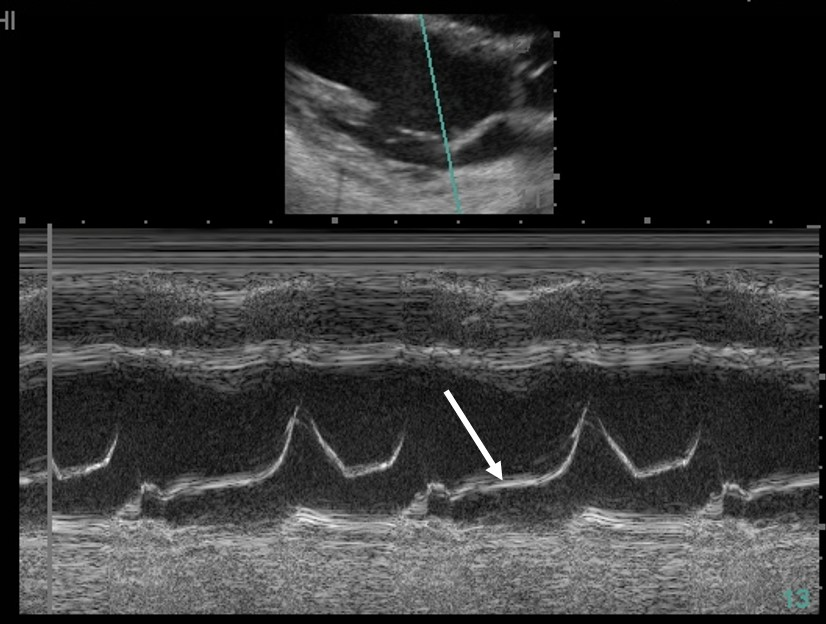

Early septic shock is often characterized by hypovolemia, reduced left ventricular afterload, and increased inotropy, conditions that favor intraventricular flow obstruction (IVO). Left ventricular hypertrophy may contribute, especially in patients with hypertrophic obstructive cardiomyopathy (HOCM), but IVO is seen in roughly 20% of all patients in early sepsis. Dynamic obstruction is usually localized to the left ventricular outflow tract (LVOT) and due to systolic anterior motion of the mitral valve as flow acceleration tends to draw the anterior leaflet into the LVOT (Bernoulli effect). IVO is sometimes seen in the midventricle, particularly in association with takotsubo cardiomyopathy. In this case, M-mode imaging across the mitral valve shows normal valve opening during diastole but abnormal anterior motion of the anterior mitral leaflet during systole, or systolic anterior motion (SAM) (Figure 3). For comparison, both mitral leaflets should remain opposed throughout systole (Figure 2, arrow). The case patient also has HOCM (interventricular septum measures 1.9 cm). Other echocardiographic findings of SAM include turbulent flow visualized as a mosaic pattern on color Doppler imaging; early systolic closure of the aortic valve and fluttering of the aortic valve leaflets; and high, late-peaking flow seen on continuous-wave Doppler imaging through the LVOT.

Normal M-mode of mitral valve showing the expected position of the anterior mitral leaflet during systole (arrow).